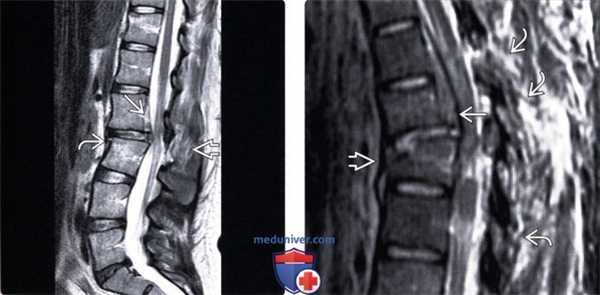

(Слева) На сагиттальном STIR МР-И отмечается усиление сигнала в области дуг С1-С2, связанное с разрывом межостистой связки, и гиперинтенсивность сигнала по дорзальной поверхности зубовидного отростка, отражающая повреждение поперечной связки.

(Справа) STIR МР-И, сагиттальная проекция: повреждение ППС и ЗПС, а также оттеснение дурального мешка кзади, связанное с эпидуральным кровоизлиянием. Также здесь имеет место контузия спинного мозга, характеризующаяся усилением интенсивности сигнала.